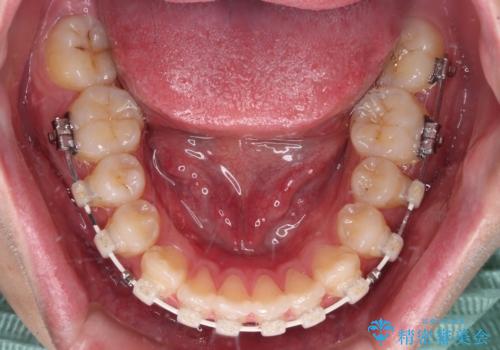

- 矯正装置

- 審美装置

治療装置については、自己管理が煩わしいとのことで、マウスピースではなく目立ちにくいワイヤー装置を選択されました。

また、治療期間中のプラークコントロールが悪く、ブラッシング指導も奏功しなかったため、装置の周りが脱灰した状態(初期むし歯)となってしまいました。